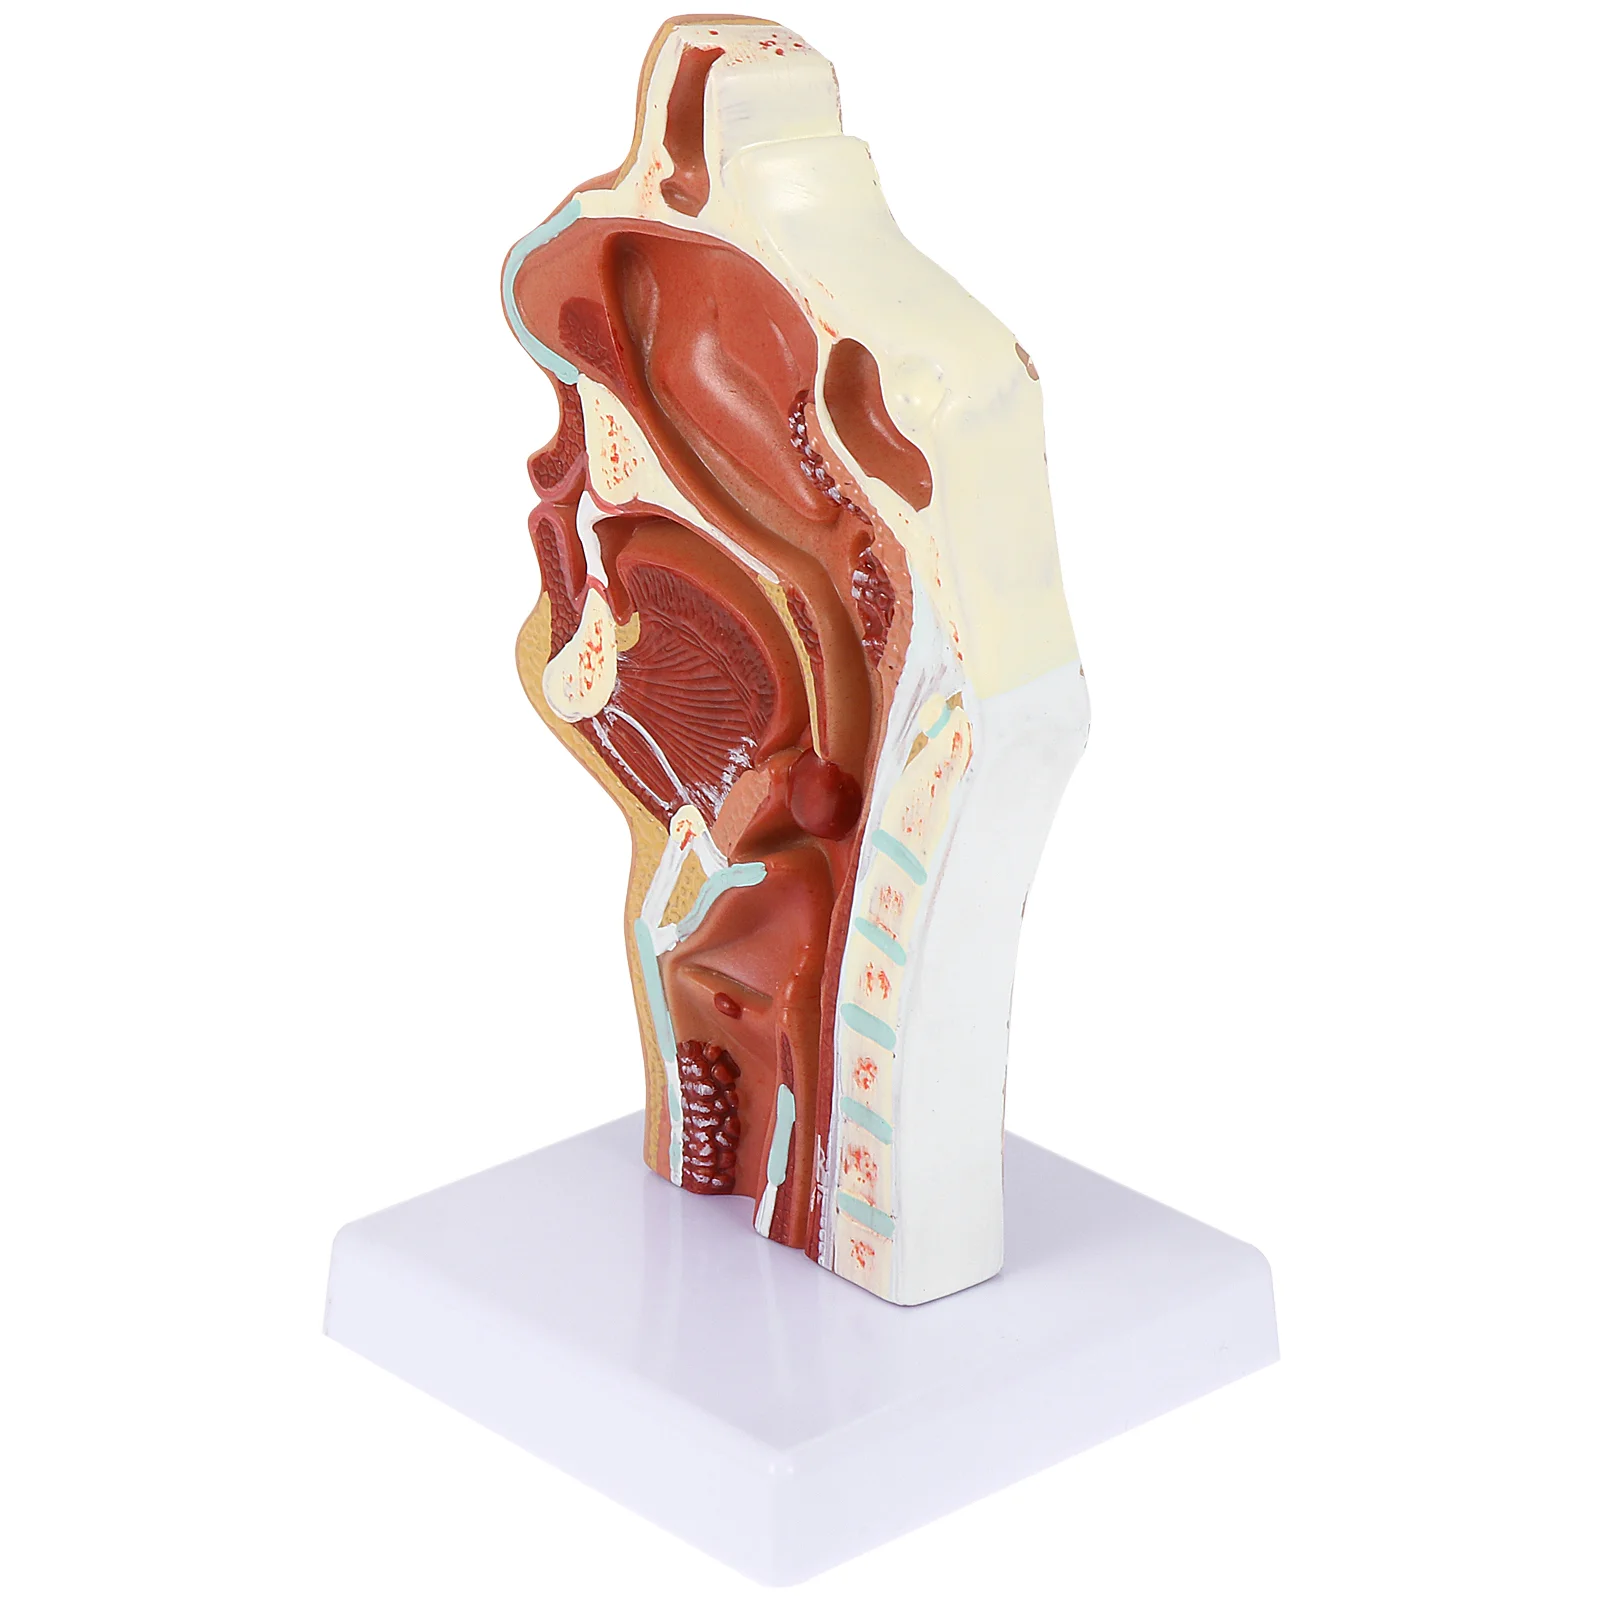

Cavity Model Anatomy Nasal Oral Anatomical Teaching Simulation Classroom Throat Tool Demonstration Models Display Body Education

aliexpress.com

$28.64